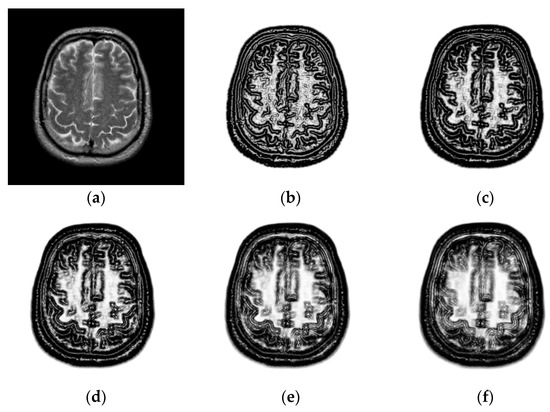

2.2. Structural Representation